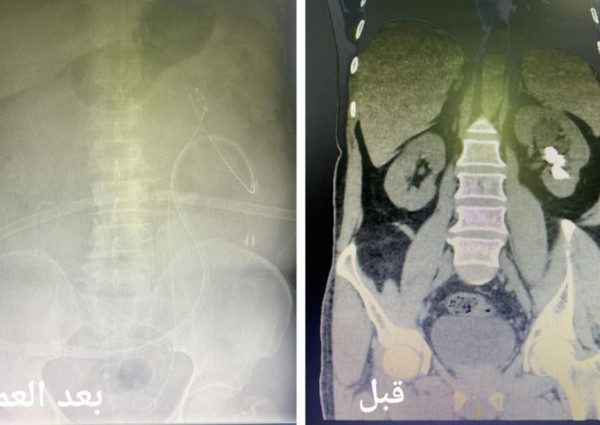

أكثر من ساعتين لإزالة حصوات كلوية لمريض بجدة

تمكن فريق طبي متخصص بعلاج أمراض المسالك البولية من إنهاء معاناة مريض استمرت 3 سنوات بإستخراج حصوات بعملية جراحية تقنية دقيقة إستمرت لأكثر من ساعتين تكللت ولله الحمد بالنجاح .وقالت صحة جدة أن فريق طبي ...